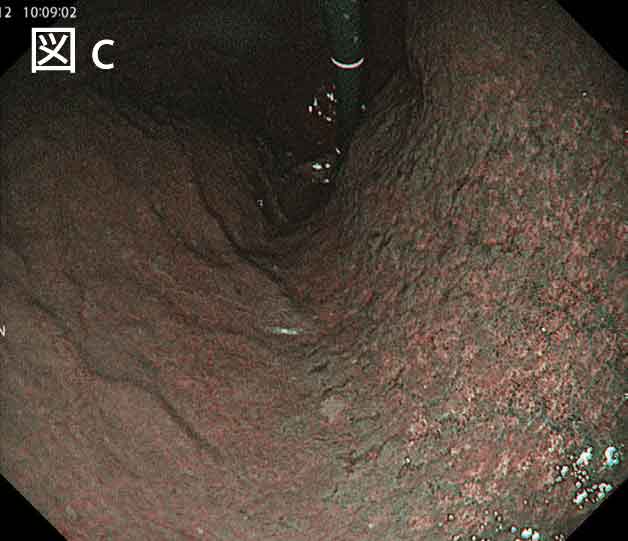

まず、従来NBI観察では主に拡大観察を併用することにより胃粘膜の微細血管構造、表面微細構造を評価し早期胃癌の診断や、腫瘍の病変範囲診断に有用な観察法として広く普及しておりますが、その名の通り、白色光に比較し波長の短い狭帯域光を使用する性質上、特に遠景が暗くなり視認性が低下することが問題でした。EVIS X1およびGIF-1200NでのNBI観察では、従来と比較し遠景の明るさが向上したために遠方の視認性が向上し、かつハイビジョン画像処理により近景の表在構造、血管が明瞭に確認できるようになりました(図c)。